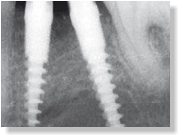

Versorgung einer Molarenlücke mit zwei Champions 3,0 mm

Durchmesser, Längen 12 mm und 16 mm und einer sofort angefertigten

Cerec-Krone in zwei Stunden. Die Krone ist rotationsgesichert,

ästhetisch wie ein natürlicher Zahn zu versorgen und auch im

Hauptbelastungszentrum sofort belastbar.

Der 4. Fall zeigt die abgeschlossene Implantation regio 15 und die

sofortversorgten, verblockten Kronen 16 und15. Auch die ästhetischen

Ergebnisse sind - ohne großen Aufwand - langzeitstabil und mehr als

zufriedenstellend.